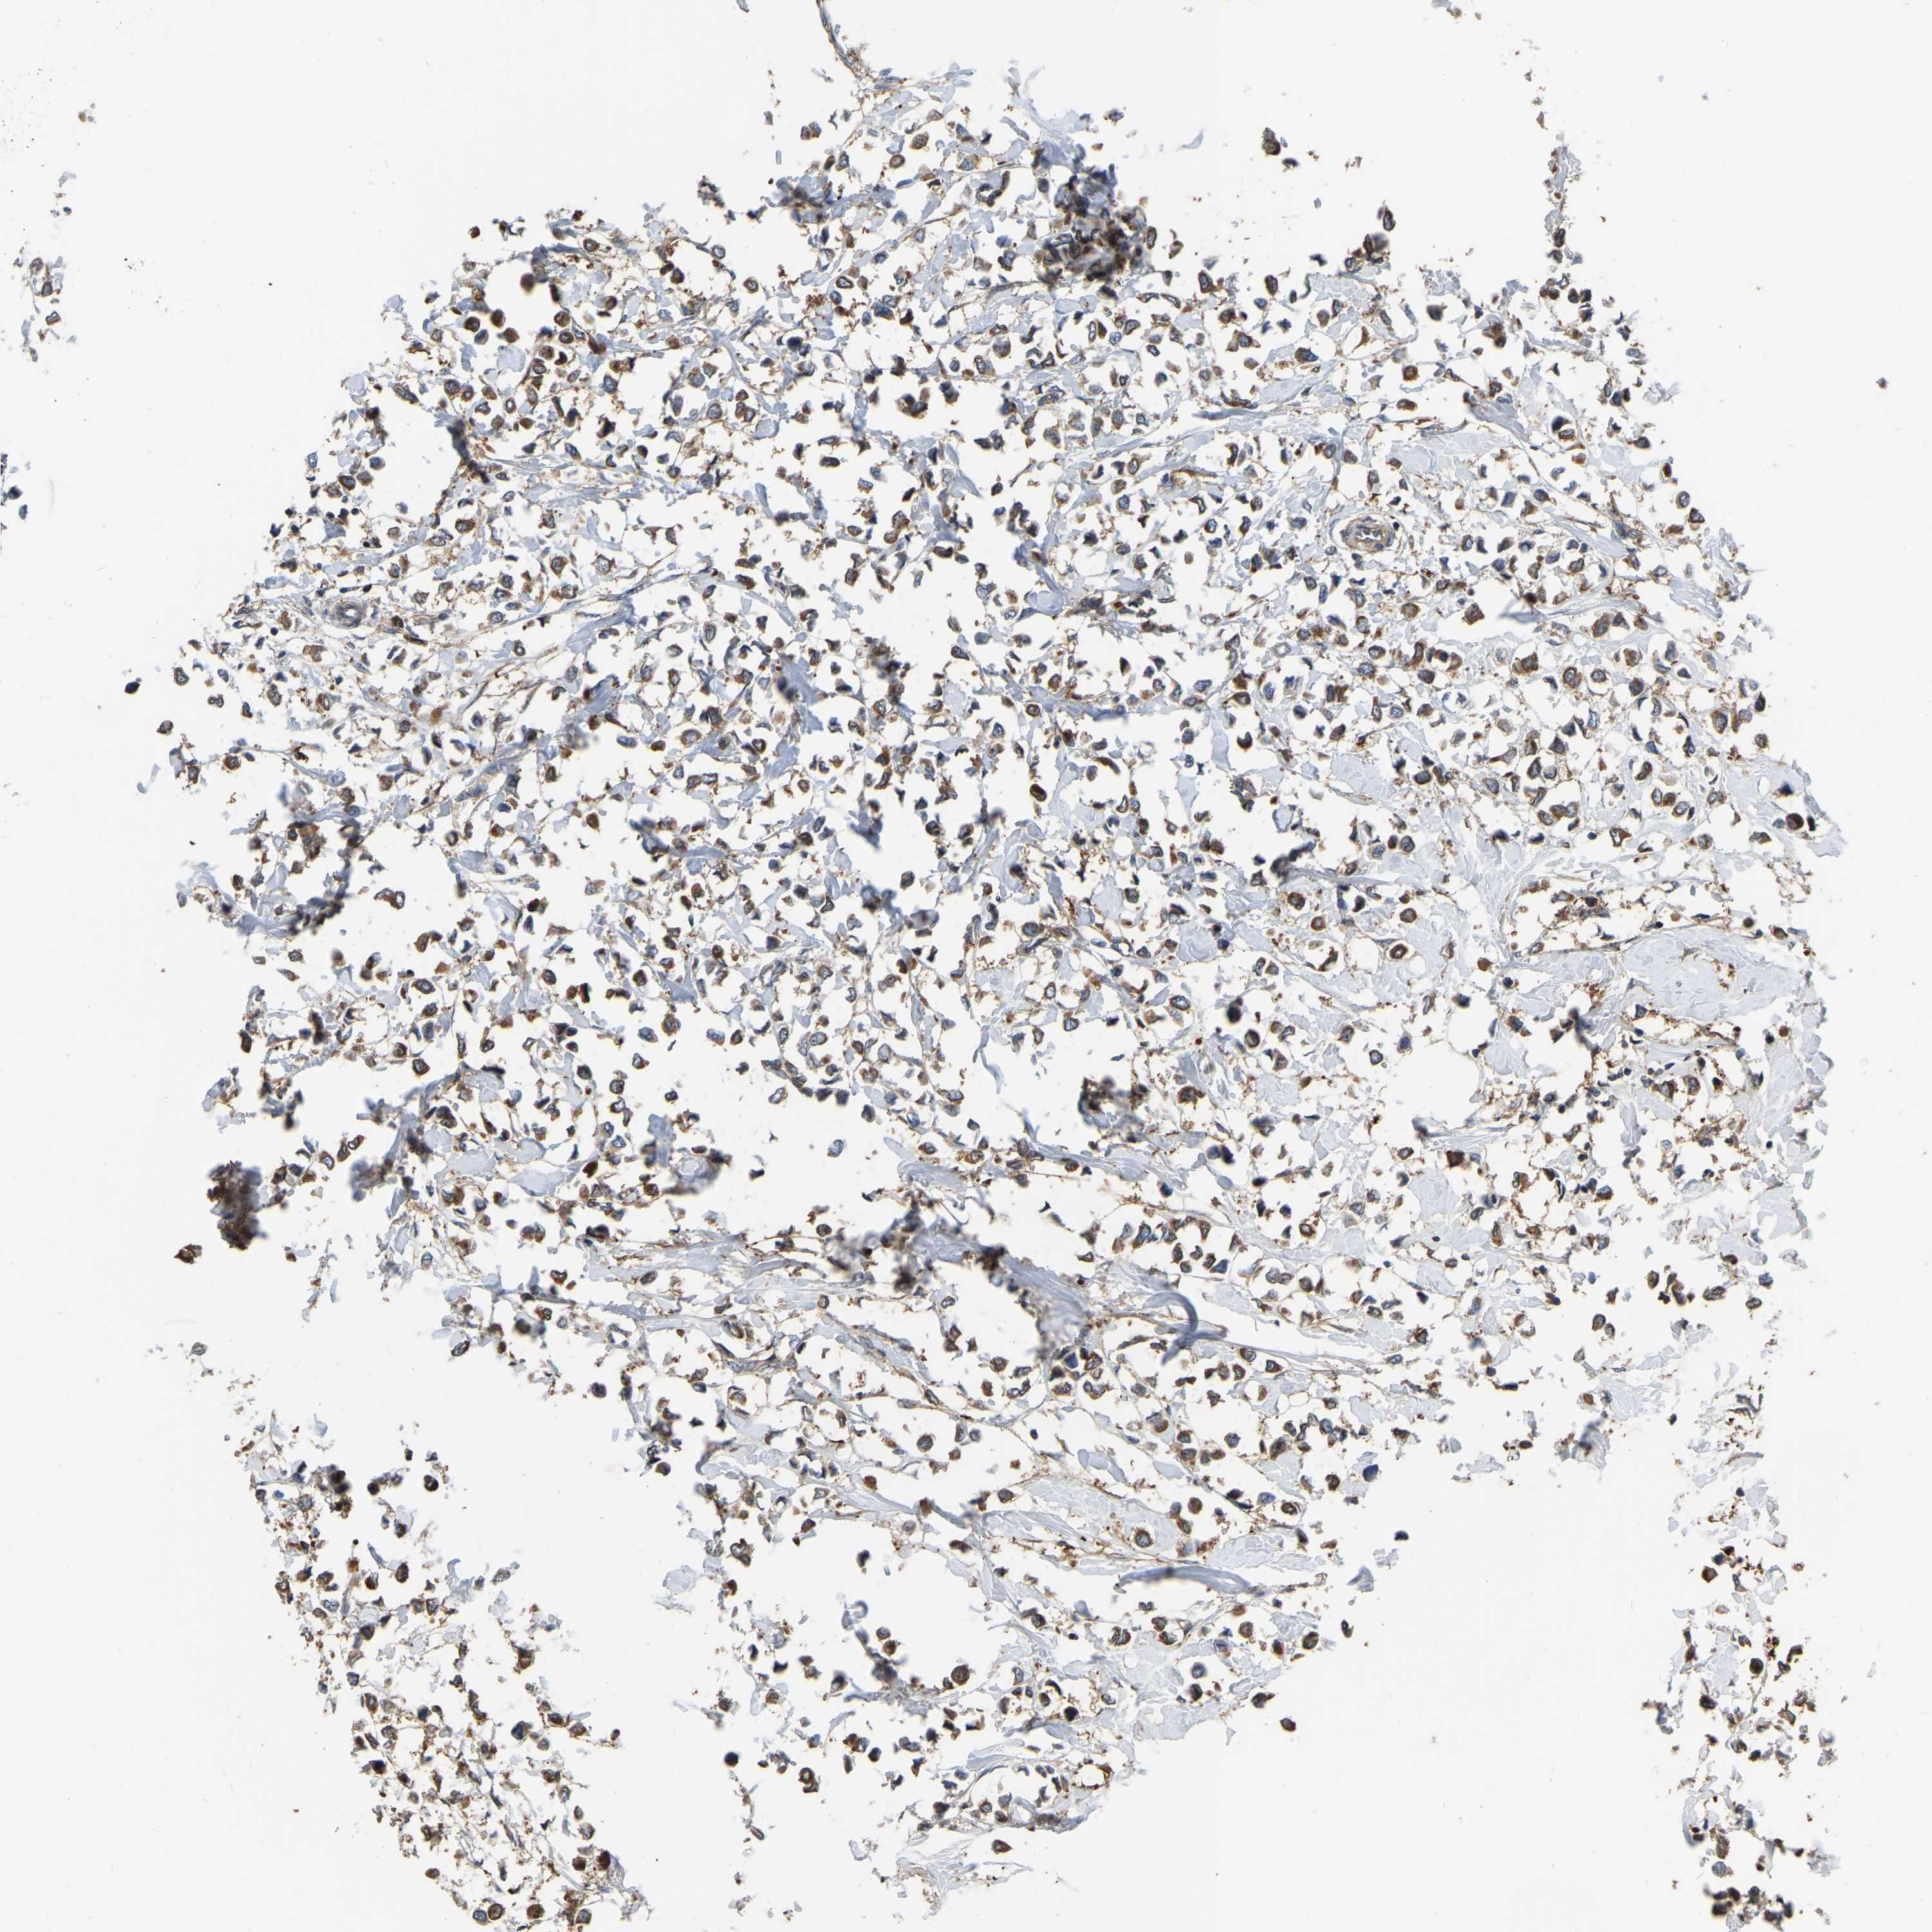

BRCA TCGA BRCA VALIDATION PROTEIN EXPRESSION

Breast cancer

Human cancer